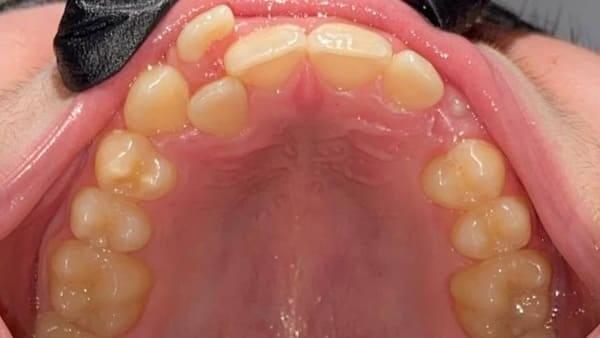

Підлітковий вік — це вирішальний час для остаточного формування прикусу та естетики обличчя. Це ідеальний період для ортодонтичних маніпуляцій, адже саме зараз можна досягти максимального результату з мінімальними зусиллями.

Кісткова тканина в підлітковому віці ще є податливою, що дозволяє досягти чудових результатів значно швидше та з меншим дискомфортом, ніж у дорослих. Нерідко результати, досягнуті в цьому віці, неможливо отримати в дорослому без складних хірургічних втручань.

Наш ортодонт спеціалізується на роботі з підлітками та володіє різними техніками та інструментами для корекції прикусу:

ми використовуємо різні види брекетів — металеві, керамічні, самолігуючі. Це дозволяє індивідуально підібрати систему, яка буде найефективнішою та найкомфортнішою для вашої дитини.

для тих, хто шукає більш естетичне та комфортне рішення, ми пропонуємо лікування за допомогою прозорих елайнерів. Вони дозволяють гармонізувати прикус, залишаючись майже непомітними.